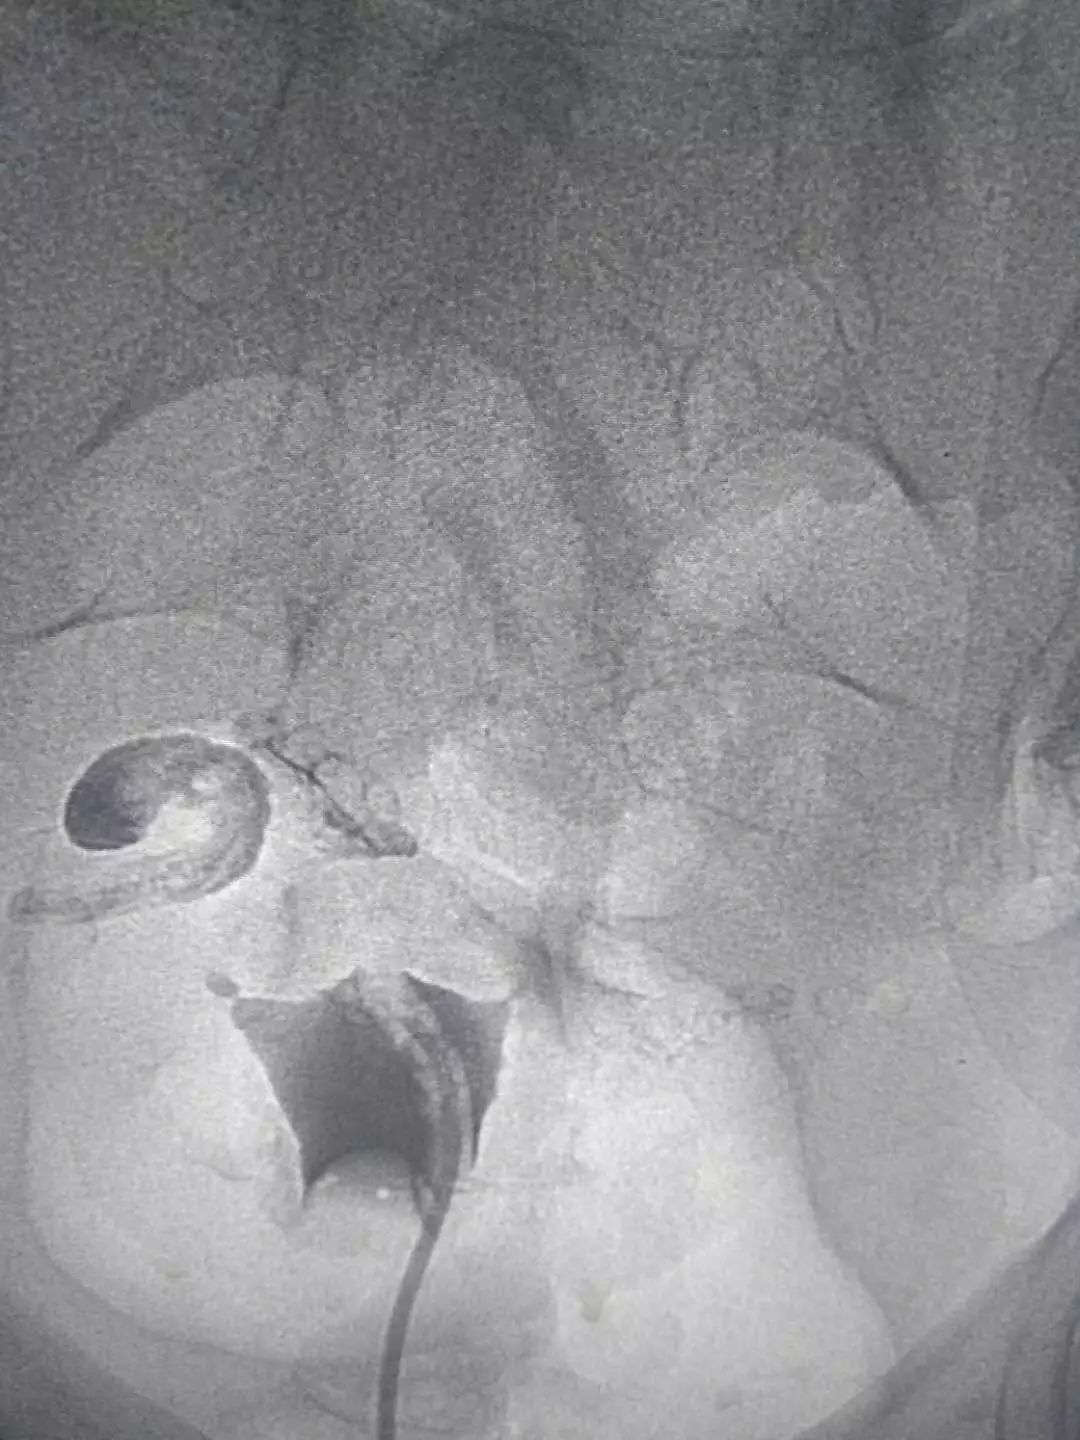

这是我院介入科开展的其中一例输卵管再通术:

患者四年前由于一次流产,之后一直不孕,在当地行子宫输卵管造影发现右侧有输卵管狭窄,当时采取保守治疗。四年来一直未孕。经过沟通,她在我院接受了输卵管介入复通术治疗。

造影视:双侧输卵管近段狭窄,右侧伞端通而不畅,左侧输卵管管壁不规则,通而不畅。

依次开通右侧输卵管+灌注药物,左侧输卵管+灌注药物,造影,显示左侧输卵管完全通畅。